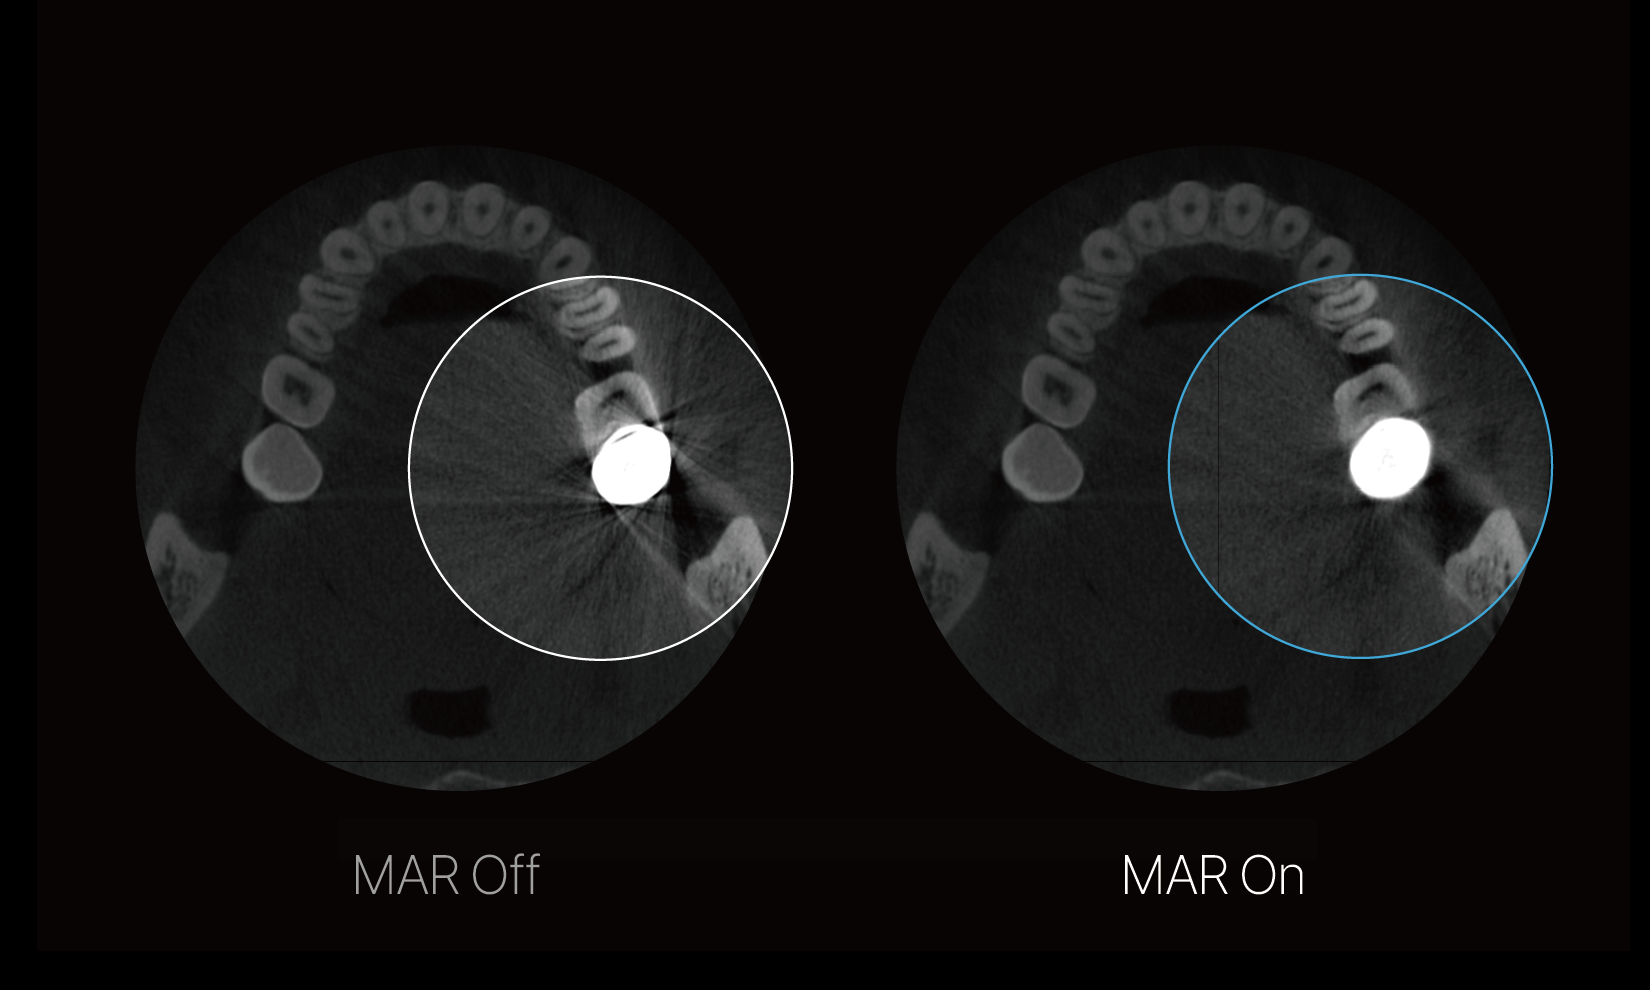

High-resolution imaging: Metal Artifact Reduction

RAYQuantum is a CBCT with MAR technology that reduces metal artifacts, resulting in more precise and reliable imaging, facilitating accurate diagnosis and treatment planning.

High-resolution imaging: Metal Artifact Reduction

RAYQuantum is a CBCT with MAR technology that reduces metal artifacts, resulting in more precise and reliable imaging, facilitating accurate diagnosis and treatment planning.